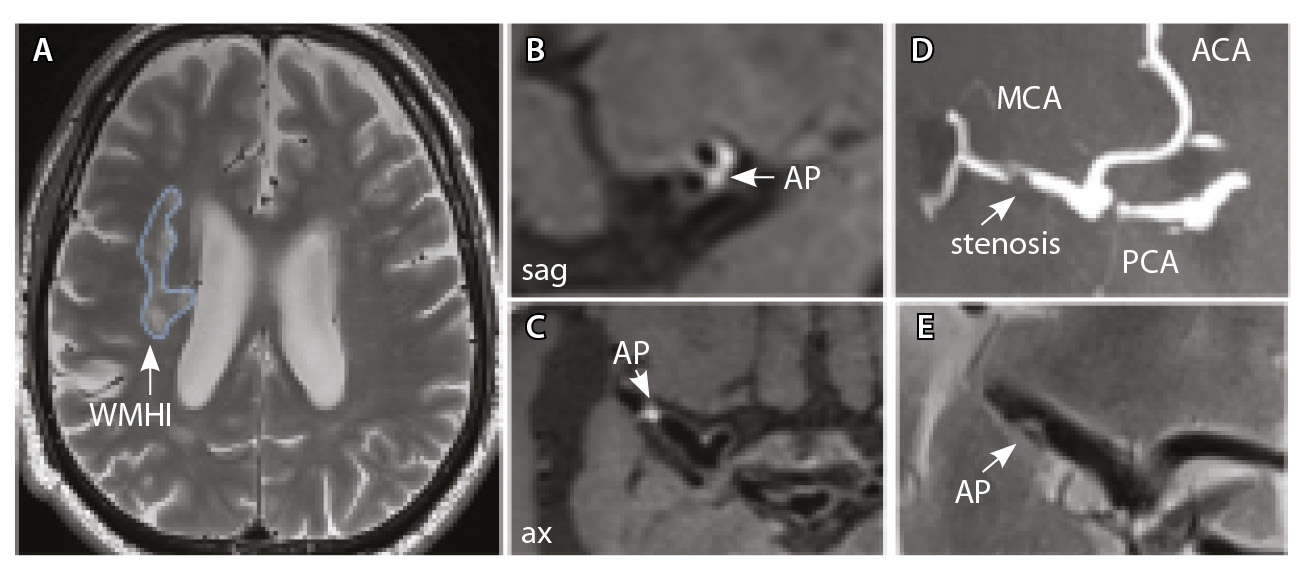

У всех включенных в исследование пациентов определялись атеросклеротические изменения брахиоцефальных артерий, в том числе на интракраниальном уровне, разной степени выраженности. У 9 больных отмечались признаки отрицательного ремоделирования артерий – выявление АСБ в стенке артерий, без сужения их просвета. Присутствовали изменения вещества головного мозга: инфаркты, в том числе лакунарные, – в 17 (58%) наблюдениях; МРТ-признаки церебральной микроангиопатии (ЦМА) – у 20 (68%) пациентов, среди них со степенью выраженности (F) по шкале Fazekas: F1 – у 7 (35%), F2 – у 4 (20%) (рис. 3), F3 – у 9 (45%) (рис. 4) [27]. Средние, большие и обширные инфаркты мозга зарегистрированы у 6 (20%) больных. Для количественной оценки изменений АСБ выбирался наиболее пораженный участок артерий (за исключением окклюзии): в 12 (41,4%) случаях это был интракраниальный сегмент внутренней сонной артерии (ВСА), в 10 (34,5%) – средней мозговой артерии (СМА), в 6 (20,7%) – базилярной артерии (БА), в 1 (3,4%) – задней мозговой артерии (ЗМА) (см. табл. 1).

Рис. 3. Пациент Ц., 53 года, с признаками церебральной микроангиопатии (F3 по шкале Fazekas), атеросклерозом интракраниальных артерий, без формирования гемодинамически значимых стенозов. А – магнитно-резонансная томография (МРТ) головного мозга, режим Т2-взвешенного изображения: видны обширные сливные зоны гиперинтенсивности белого вещества (ГИБВ) с наличием на этом фоне лакунарных инфарктов; Б, В, Г – МРТ сосудистой стенки, режим T1-TSE-db-FS после контрастного усиления: в сегменте М1 левой средней мозговой артерии (СМА) визуализируется эксцентричная атеросклеротическая бляшка (АСБ), интенсивно накапливающая контрастный препарат; Д – трехмерная магнитно-резонансная времяпролетная (3D ToF) ангиография: выявляется неровность контуров левой СМА в сегменте М1; ax – аксиальная, sag – сагиттальная, cor – коронарная плоскости; ВСА – внутренняя сонная артерия; ПМА – передняя мозговая артерия

Рис. 4. Пациент К., 69 лет, с признаками церебральной микроангиопатии (F2 по шкале Fazekas) и атеросклерозом интракраниальных артерий, с формированием гемодинамически значимого стеноза в сегменте М1 правой средней мозговой артерии (СМА): А – магнитно-резонансная томография (МРТ), режим Т2-взвешенного изображения: видны множественные сливные очаги гиперинтенсивности белого вещества (ГИБВ); Б, В – МРТ сосудистой стенки, режим T1-TSE-db-FS после контрастного усиления: в сегменте М1 правой СМА визуализируется эксцентричная атеросклеротическая бляшка (АСБ), интенсивно накапливающая контрастный препарат; Г – трехмерная магнитно-резонансная времяпролетная (3D ToF) ангиография: виден стеноз правой СМА в сегменте М1; Д – режим HR Т2-TSE: видна АСБ в сегменте М1 правой СМА; ax – аксиальная, sag – сагиттальная плоскости; ЗМА – задняя мозговая артерия; ПМА – передняя мозговая артерия